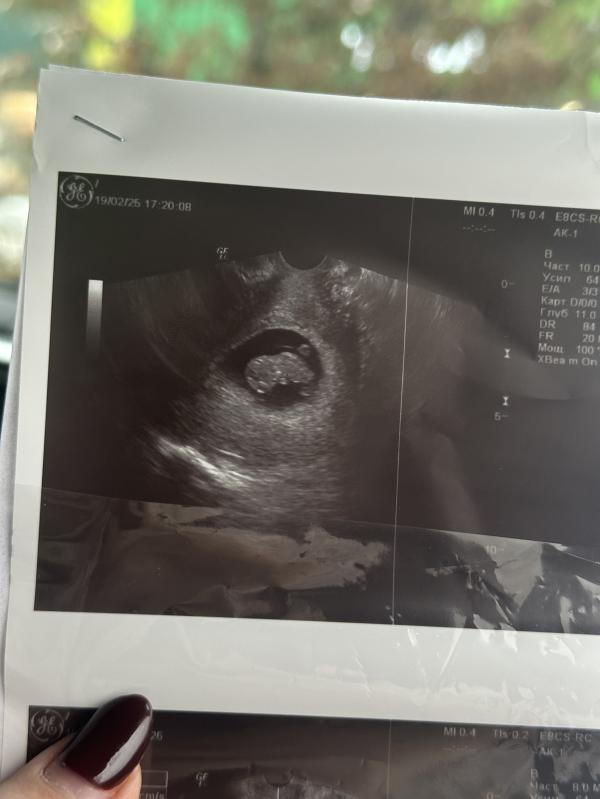

Малыш уже 2,5 см и шевелится! Как пережить эти эмоции?

Вчера были на узи, малыш уже 2,5 см😍

Уже во всю там шевелит ножками и ручками, очень активный 🥹❤️